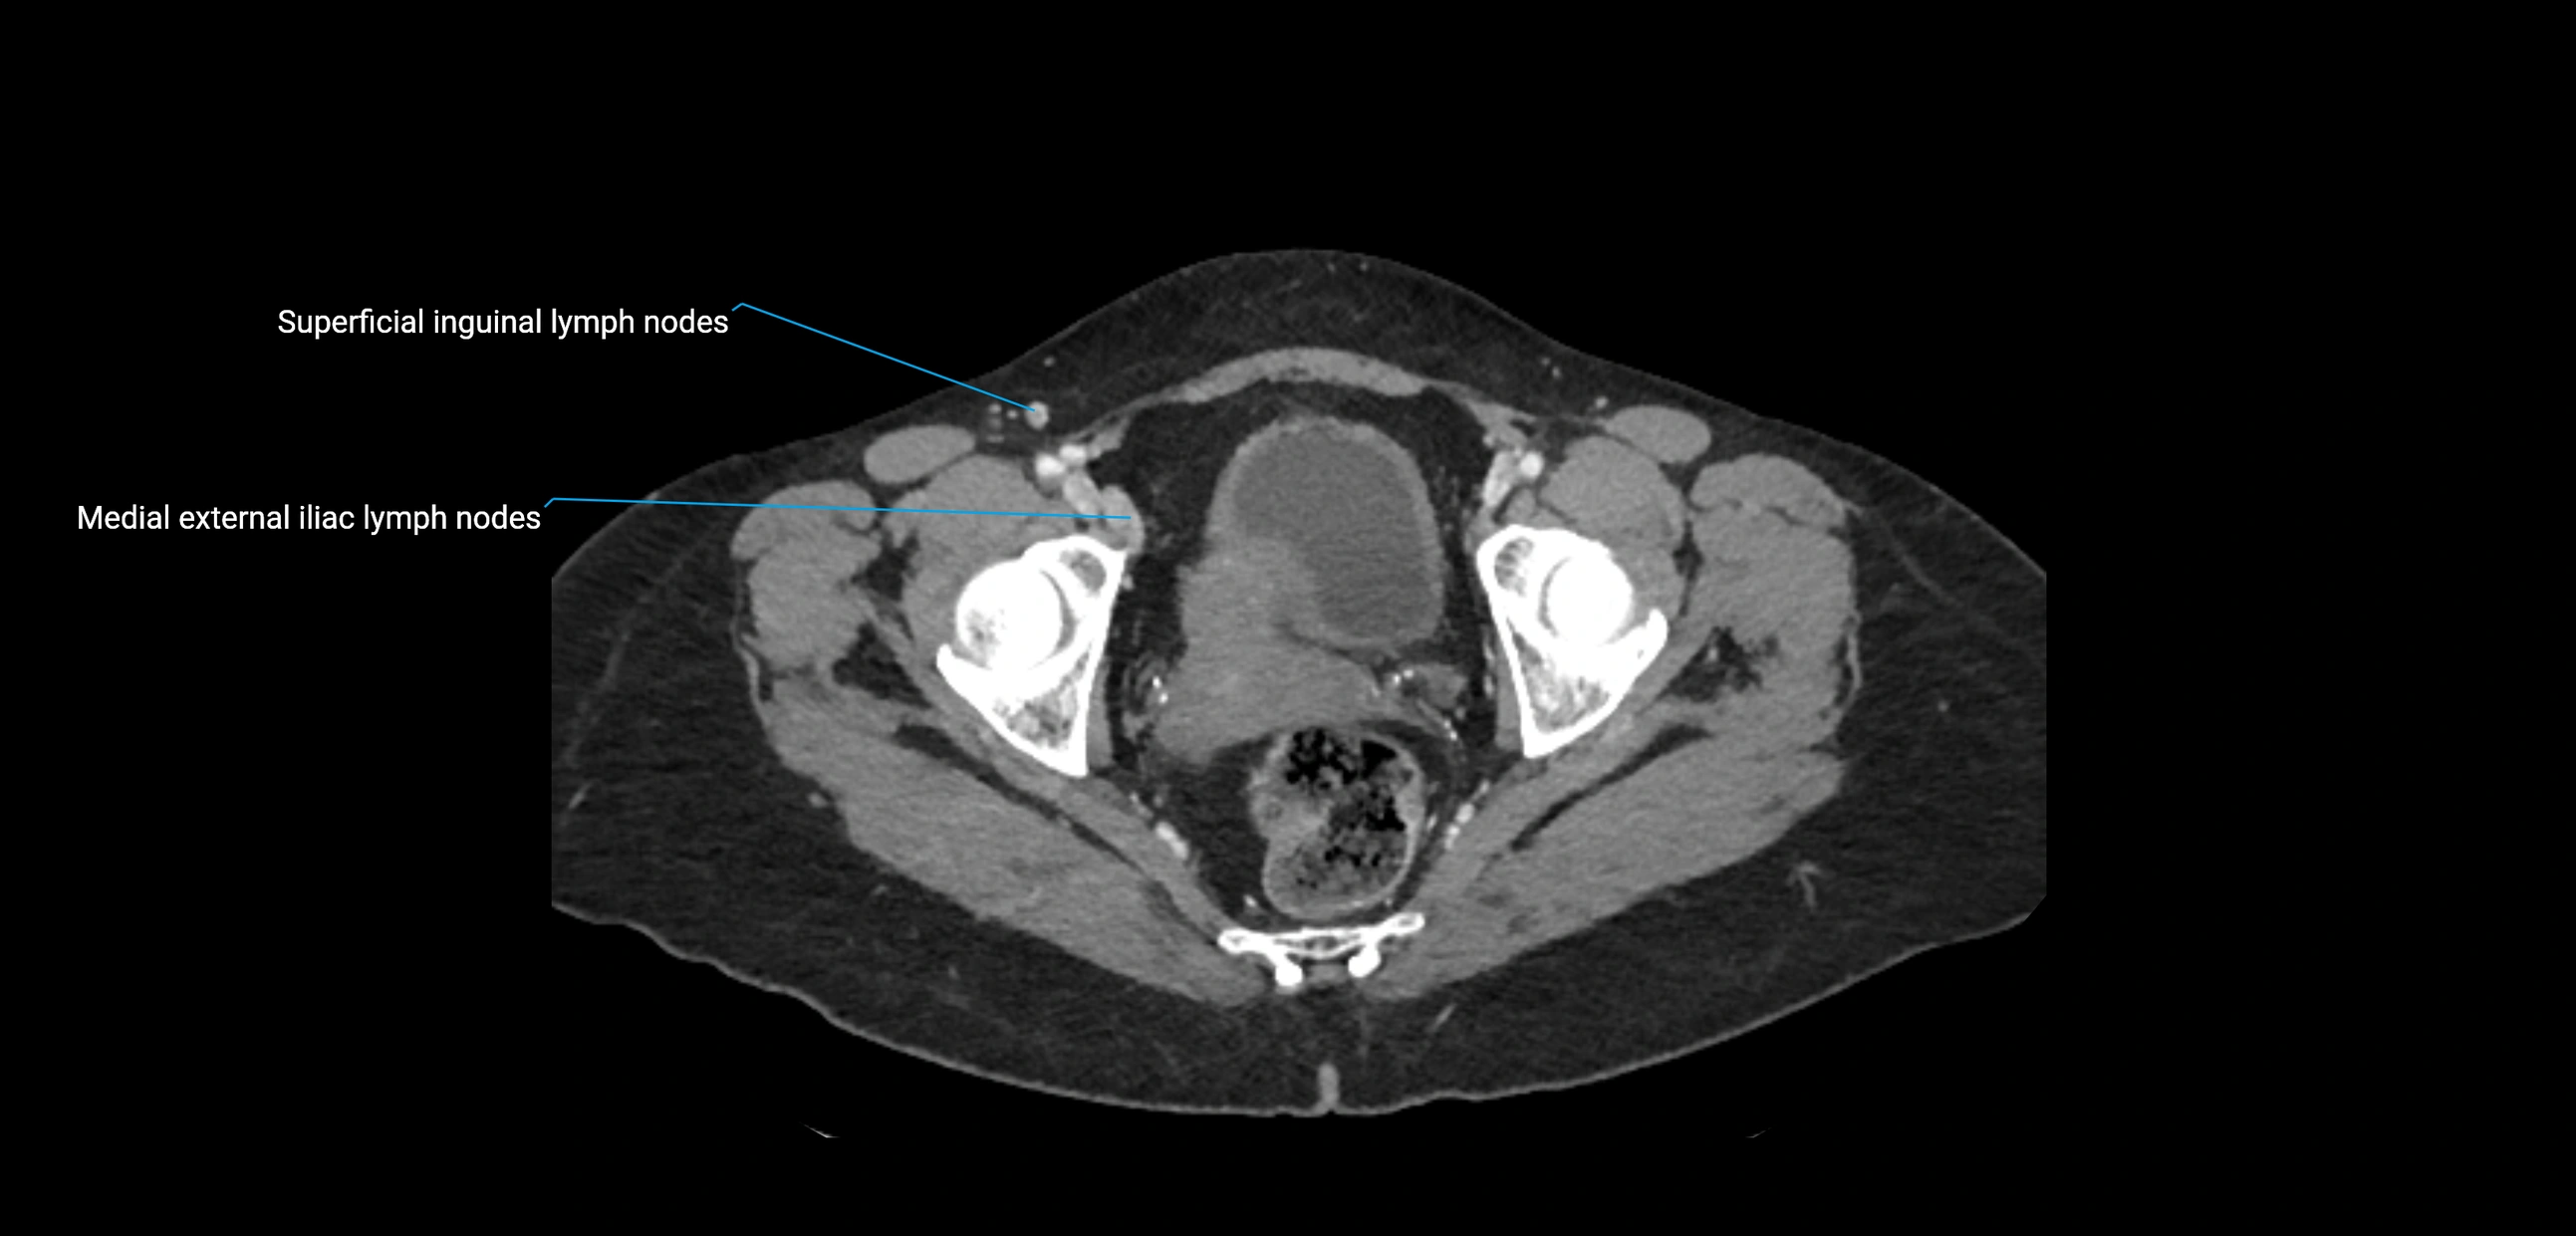

CT Appearance

CT Pre-Contrast:

• Nodes appear as soft-tissue density nodules adjacent to the aorta and IVC

• Calcification may be seen in chronic infections (e.g., tuberculosis)

CT Post-Contrast:

• Normal nodes enhance homogeneously

• Malignant nodes may show heterogeneous enhancement, central necrosis, or conglomerate formation

• Size >1 cm short axis is suspicious, though morphology and distribution are equally important